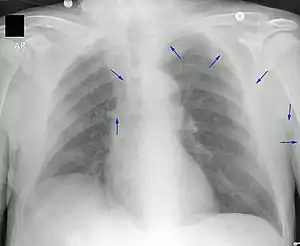

A PICC is inserted in a peripheral vein such as the cephalic vein, basilic vein or brachial vein in the arm, and then threaded through the veins toward the heart, until the end of the catheter rests in the proximal superior vena cava or cavoatrial junction. They must be inserted by a trained medical professional, including a physician, but also any trained medical professional such as a specially trained registered nurse.[5] An ultrasound or chest X-ray, or the use of fluoroscopy, can be used during insertion and to confirm placement. The insertion is a sterile procedure, but does not need to be performed in a completely sterile environment like an operating room.